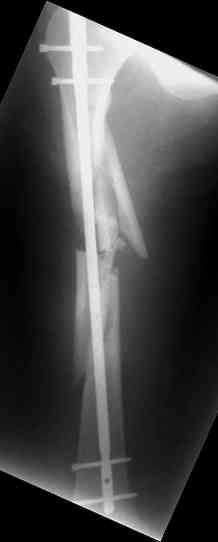

Надеюсь сейчас показать перелом, а потом синтез.

Имя     : 2.jpg

Тип     : image/jpeg

Размер  : 9216 байтов

Описание: отсутствует

Url     : http://weborto.net:8080/pipermail/ortho/attachments/20070925/7aabe9cf/attachment-0006.jpg